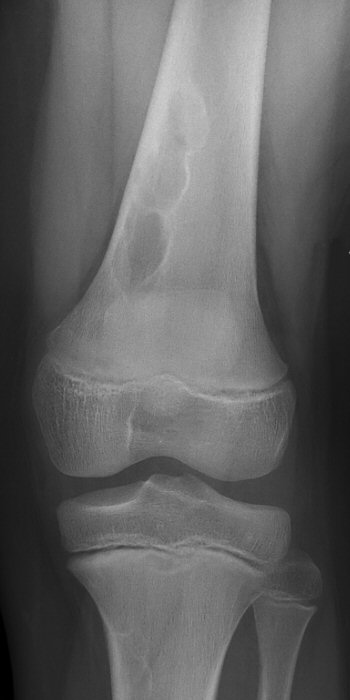

- Non-ossifying fibroma = NOF: felaktig ossifikation, oftast hos pojkar 5-15 år i metafys av långa rörben, lytiskt, "bubbligt" utseende med sklerotiska kanter. Kan ge fraktur som i så fall behandlas på vanligt sätt. Kan någon enstaka gång opereras med curettage och bengraft vid stor påverkan på kortex med frakturrisk. Brukar annars läka spontant, kan följas med röntgenkontroller årligen. [2]

Två exempel på NOF i distala femur